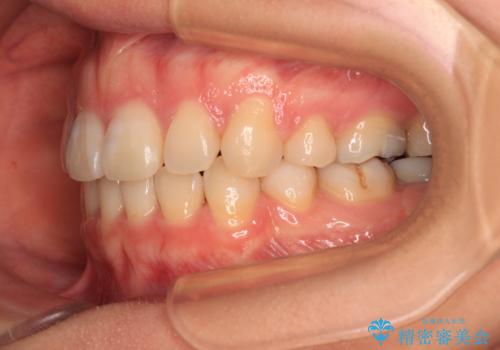

上下前歯がくちばしのように突出していましたが、抜歯矯正により口元が引っ込み、唇が閉じやすくなり、鼻の下の膨れた感じも解消されました。